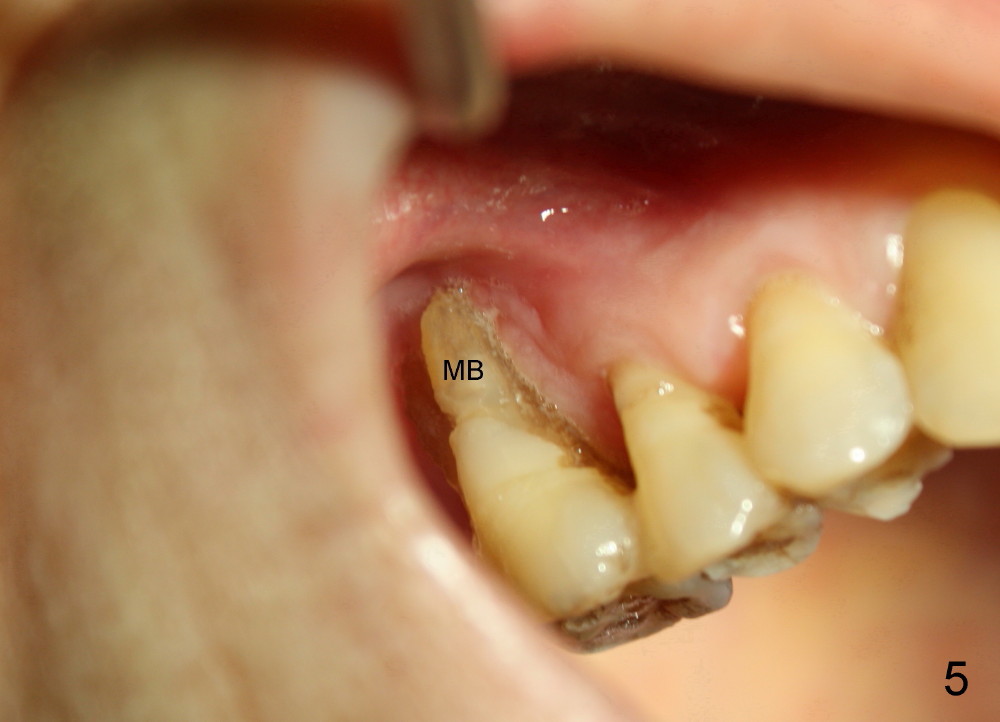

Lack of bony support and soft tissue coverage appear to be an obstacle to immediate implant. Two cases are presented. The first one is my first attempted immediate implant patient (Fig.1-3), a 54-year-old lady. She is extremely apprehensive. The upper right first molar has severe perio-endo disease. There is no bone around the buccal roots (MB, DB in Fig.1). The tooth is non salvageable and is treated the best with an immediate implant. When the tooth is extracted, the large buccal gingival defects (Fig.2 MB, DB) and sinus perforation (Fig.3) through the palatal socket (Fig.2 *) are apparent contraindications to immediate implant. Amazingly, the gingiva heals rapidly post extraction. An implant is placed 1 month later.